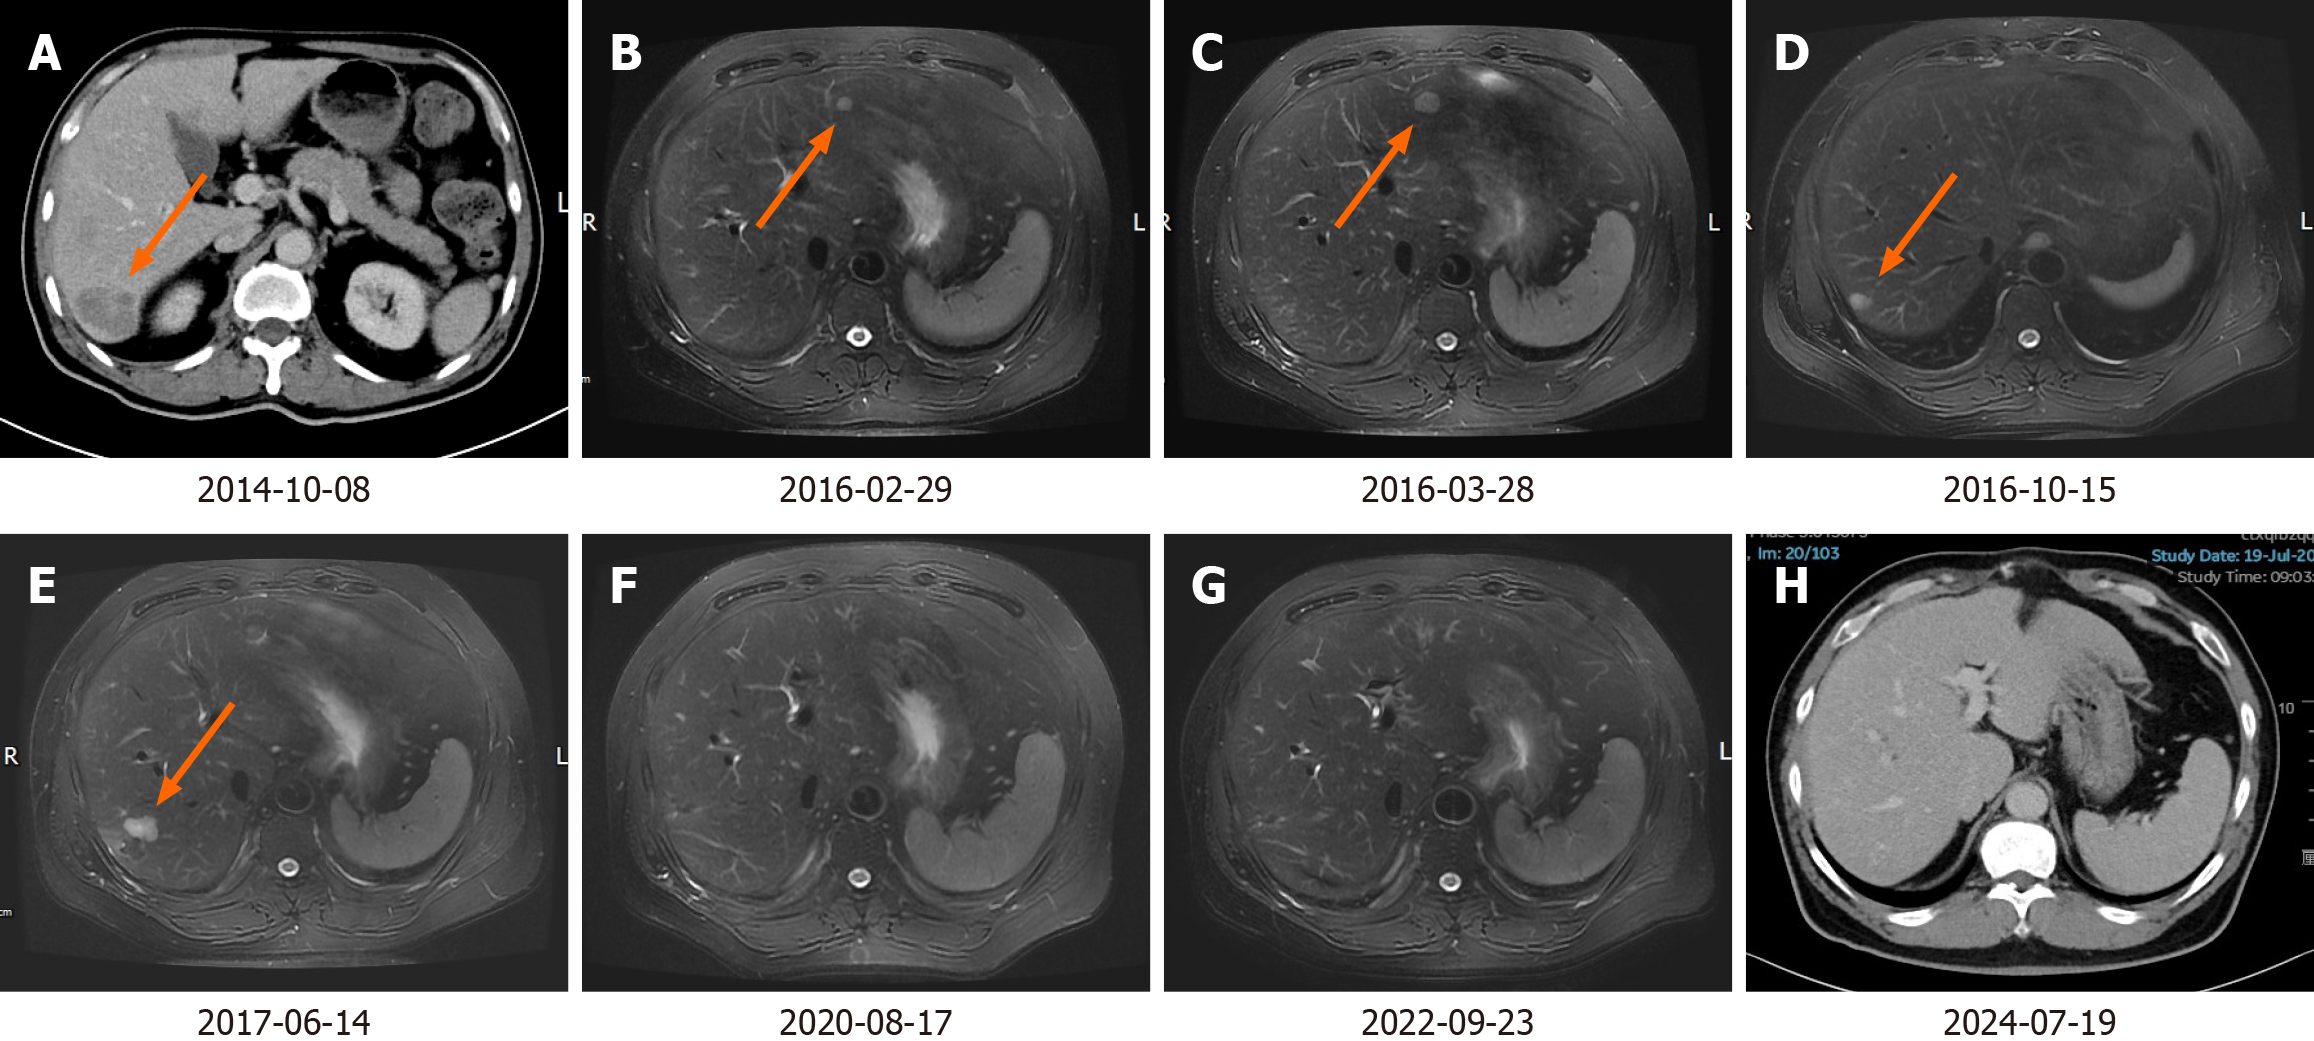

According to the National Comprehensive Cancer Network (NCCN) guidelines, PET-CT is not routinely recommended for baseline assessment prior to chemotherapy. Consequently, we performed only CECT of the chest and abdomen and no definitive new lesions were identified. From April 12, 2014, to September 16, 2014, the patient received nine cycles of chemotherapy as per mFOLFOX6 regimen (oxaliplatin, 100 mg/m2, day 1; leucovorin, 400 mg/m2, day 1-2; fluorouracil, 2400 mg/m2, once over 46 hours, day 1-3). On October 8, 2014, repeat CECT abdomen revealed a nodular lesion in the segment Ⅶ of right lobe of the liver, measuring approximately 1.9 cm, which was deemed a metastasis (Figure 2A). We did not perform a preoperative biopsy or fine needle aspiration cytology (FNAC). On October 23, 2014, the patient underwent open non-anatomical R0 resection of the LM. The surgery lasted for 3 h and 25 min, and there were no complications. The duration of the hospital stay was 11 days. The postoperative pathology confirmed LM from colon adenocarcinoma. Between November 28, 2014, and July 24, 2015, the patient underwent 12 cycles of chemotherapy using the FOLFIRI regimen (irinotecan, 200 mg/m2, day 1; leucovorin, 400 mg/m2, day 1-2; fluorouracil, 2400 mg/m2, once over 46 hours, day 1-3). On February 29, 2016, an abdominal magnetic resonance imaging (MRI) revealed punctate and small nodular abnormal signals in both the left and right lobes of the liver (Figure 2B). New metastatic foci could not be ruled out, and disease progression was suspected. The patient did not undergo biopsy, FNAC, or PET-CT. According to the NCCN guidelines, for advanced colorectal cancer, maintenance therapy with oral 5-FU agents, such as capecitabine, may be considered following the achievement of optimal efficacy with 5-FU-based mFOLFOX and FOLFIRI regimens. From March 10 to April 1, 2016, the patient received two cycles of capecitabine treatment (capecitabine, 1000 mg/m2, twice daily on days 1-14). On May 28, 2016, the MRI indicated a small nodular area exhibiting increased signal intensity in the left lobe of the liver, alongside an abnormal punctate lesion in the right lobe. The larger lesion, situated in segment IV, measures approximately 1.4 cm × 1.7 cm (Figure 2C). On May 30, 2016, RFA of left lateral lobe LM was performed. On October 15, 2016, the MRI demonstrated that the size of the left lateral lobe lesion had slightly decreased, with no internal enhancement. However, the lesion in the right lobe had increased in size compared to previous assessments (Figure 2D). On October 17, 2016, RFA of the right lobe LM was performed. On June 14, 2017, the MRI indicated that the lesions in the left lateral lobe and right posterior lobe had decreased in size, while several new nodules were identified in the segment Ⅵ and Ⅶ of the right lobe, suggestive of new metastatic foci (Figure 2E). Subsequently, on June 22, 2017, the patient underwent open non-anatomical resection of the right lobe LM with R0 margins. The duration of the operation was 3 hours and 5 minutes, and it proceeded without complications. The patient was discharged after a hospital stay of 10 days. The postoperative pathology indicated that the liver resection specimen measured approximately 3 cm × 2.5 cm × 4 cm. Histopathological examination revealed extensive infiltration of moderately differentiated adenocarcinoma within the liver tissue. Additionally, vascular tumor thrombi were present. Subsequently, the patient underwent follow-up examinations every six months to one year. Each examination includes routine blood tests, biochemical tests, tumor marker assessments, and CECT of the chest and abdomen. Multiple follow-up examinations have indicated no new lesions (Figure 2F and G). The most recent follow-up examination occurred on July 19, 2024 (Figure 2H).

Currently, the patient remains under observation, and his quality of life is reported to be good. The case timeline is presented in Figure 3.